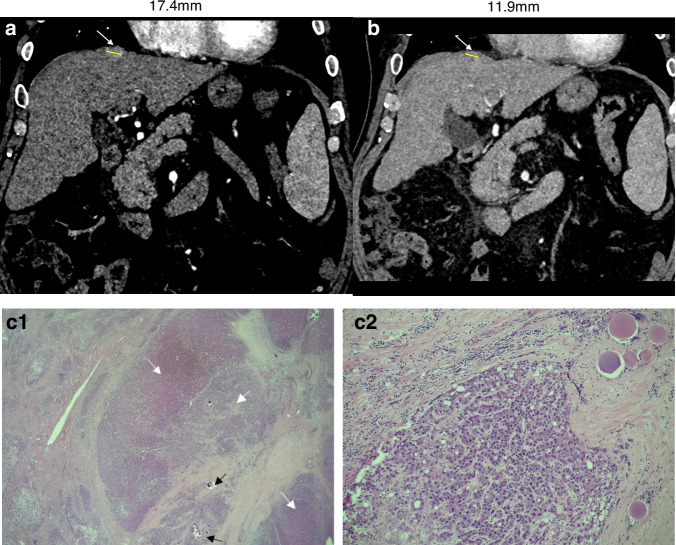

Background: Stereotactic ablative radiotherapy (SABR) has emerged as a new treatment modality for hepatocellular carcinoma (HCC). Evaluation of tumour responses following SABR are currently based on conventional radiological criteria used for locoregional therapies. Whether these criteria accurately reflect tumour responses following SABR remains unknown. In this study, we provide a direct comparison of post-SABR radiological evaluation and explant histology for patients with HCC who underwent bridging SABR prior to liver transplantation.

Methods: Patients with HCC who received SABR as bridging therapy prior to liver transplantation (January 2016-December 2022) in a large UK liver transplant centre were included. Post-SABR imaging was reported by two specialist hepato-pancreato-biliary radiologists, and histological examination of the explanted liver was performed by experienced liver histopathologists.

Results: Six patients with residual active HCC received SABR as bridging therapy prior to undergoing liver transplantation in our cohort. Of five patients with viable HCC detected on explant histology, recent radiological evaluation using LI-RADS treatment response criteria had suggested no evidence of residual active HCC for three patients, difficulty delineating residual disease from post-radiotherapy changes for one patient, and accurately identified viable tumour in one patient.

Conclusion: In our case series conventional radiological criteria underestimated HCC tumour viability following SABR compared to explant histology. As the role for SABR expands in the management of HCC, caution is needed with radiological interpretation of HCC responses to radiotherapy using standard LI-RADS criteria. Prospective study in a larger cohort is required to identify radiological criteria capable of more conclusively evaluating HCC responses to SABR.